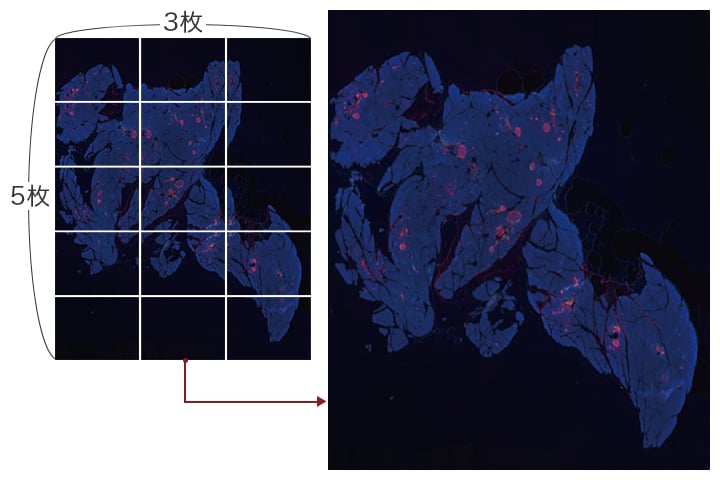

ランゲルハンス島におけるa細胞とb細胞の可視化 顕微鏡観察ラボ キーエンス